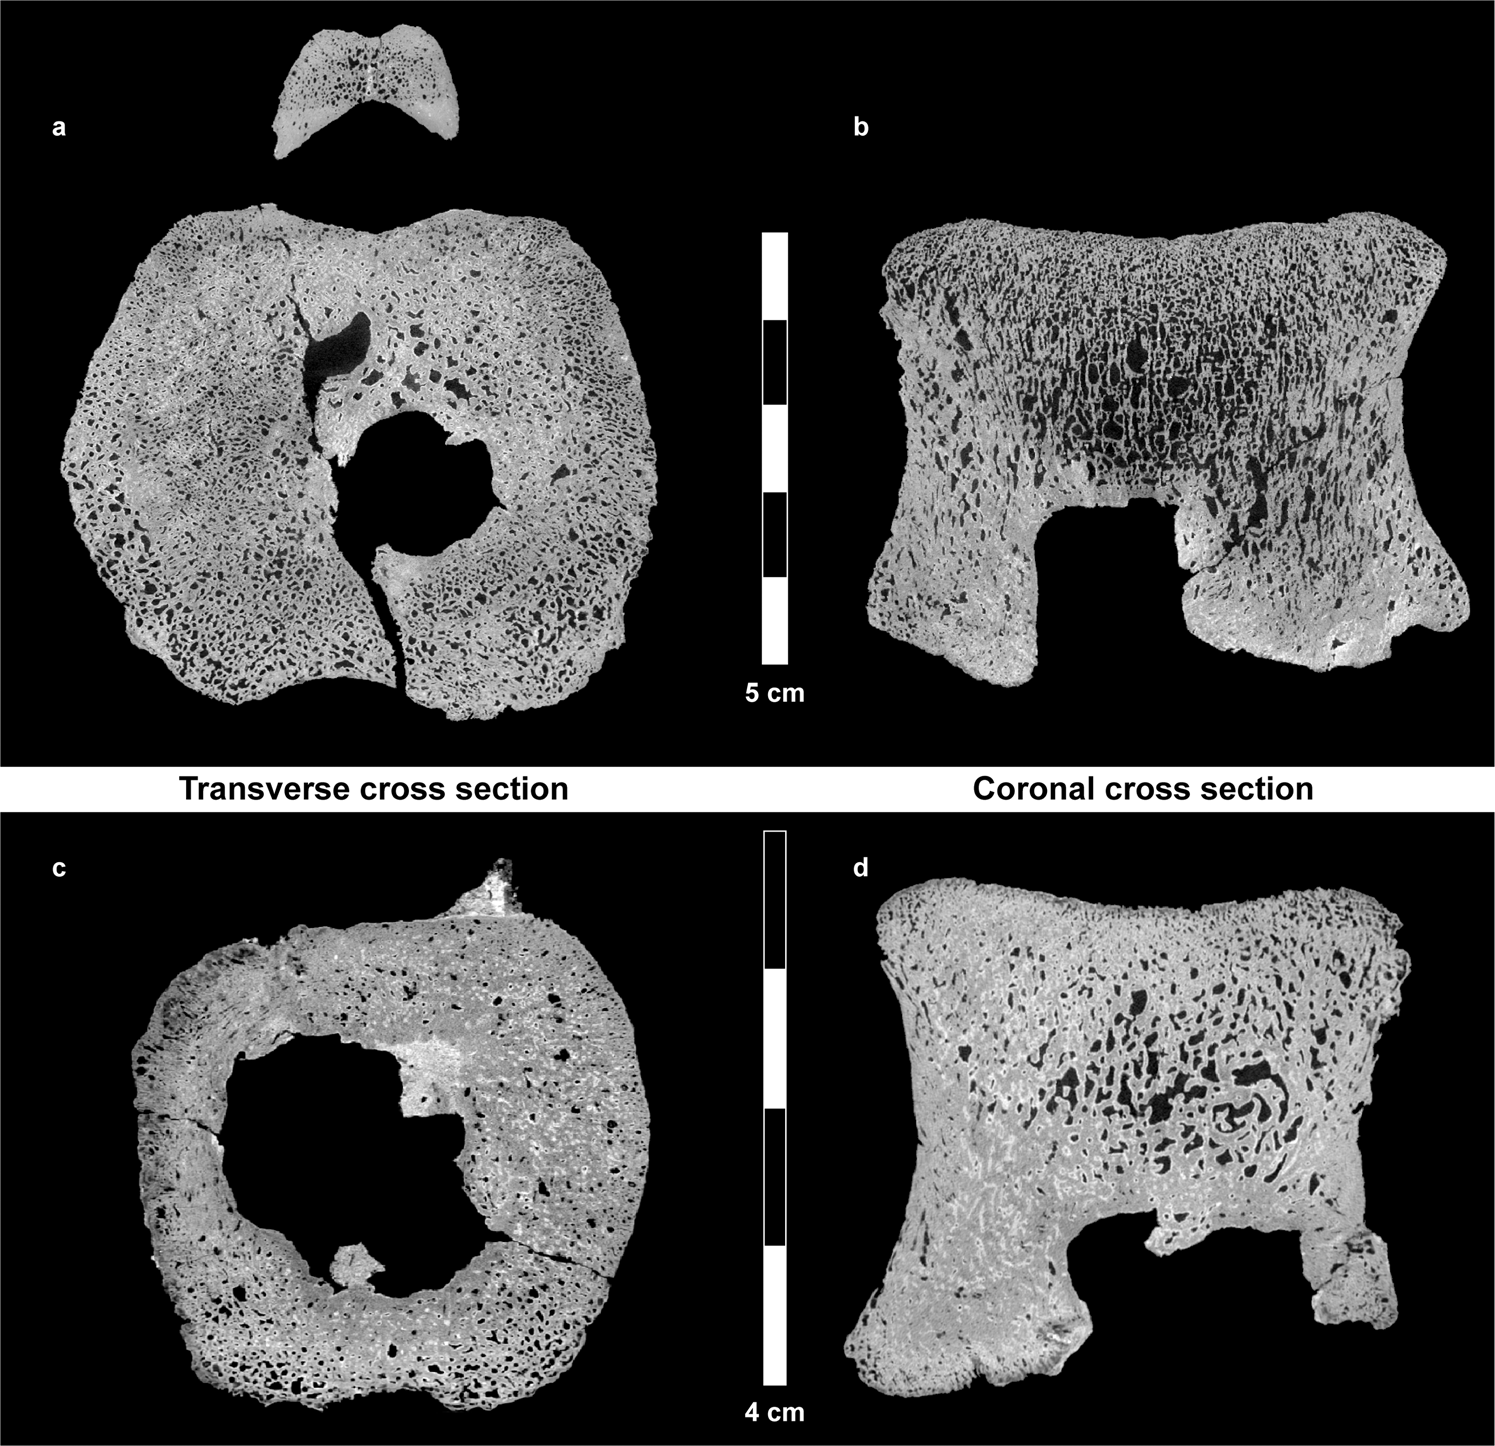

Figure 4

From: Suggested Case of Langerhans Cell Histiocytosis in a Cretaceous dinosaur

Transverse (horizontal) and coronal cross sections retrieved from the µCT scans of the large (a,b) and small (c,d) vertebrae. In some areas, there is clear evidence of bone remodeling adjacent to the tumor (sclerotic margins). Multiple lesions coalesce, thus creating a single lesion with well-circumscribed margins, having the “geographic” pattern (a term applied to a meandering border).